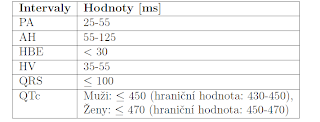

Intrakardiální EKG je grafický záznam srdeční elektrické aktivity, jenž je snímán pomocí do srdce zavedených katétrů. V tabulce 1.1 jsou uvedeny délky základních intervalů na intrakardiálním EKG při sinusovém rytmu.

| Tabulka 1.1: Důležité intervaly na intrakardiálním EKG při sinusovém rytmu [25]

Vysvětlení tabulky 1.1: PA interval je doba od počátku P vny na povrchovém EKG po 1. výchylku zaznamenanou z katétru umístěného na Hisovu svazku, tento interval podává informaci o intraatriálním vedení. AH, HV intervaly, jenž jsou zobrazeny na obrázku

1.2, se měří na intrakardiálním EKG při sinusovém rytmu pro vyhodnocení AV převodu. AH interval se měří mezi potenciálem síní a potenciálem Hisova svazku, HV interval mezi potenciálem Hisova svazku a potenciálem komor. Potenciály snímané intrakardiál-ním EKG z oblasti Hisova svazku jsou označovány zkratkou HBE. QRS je délka QRS komplexu a QTc je korekční QT interval, jedná se o QT interval s korekcí na tepovou frekvenci:

V praxi se používá spíše QTc než QT, protože není ovliňován RR srdeční frekvencí. S výskytem delších QTc intervalů stoupá pravděpodobnost výskytu maligní komorové tachykardie. [4, 22, 31]